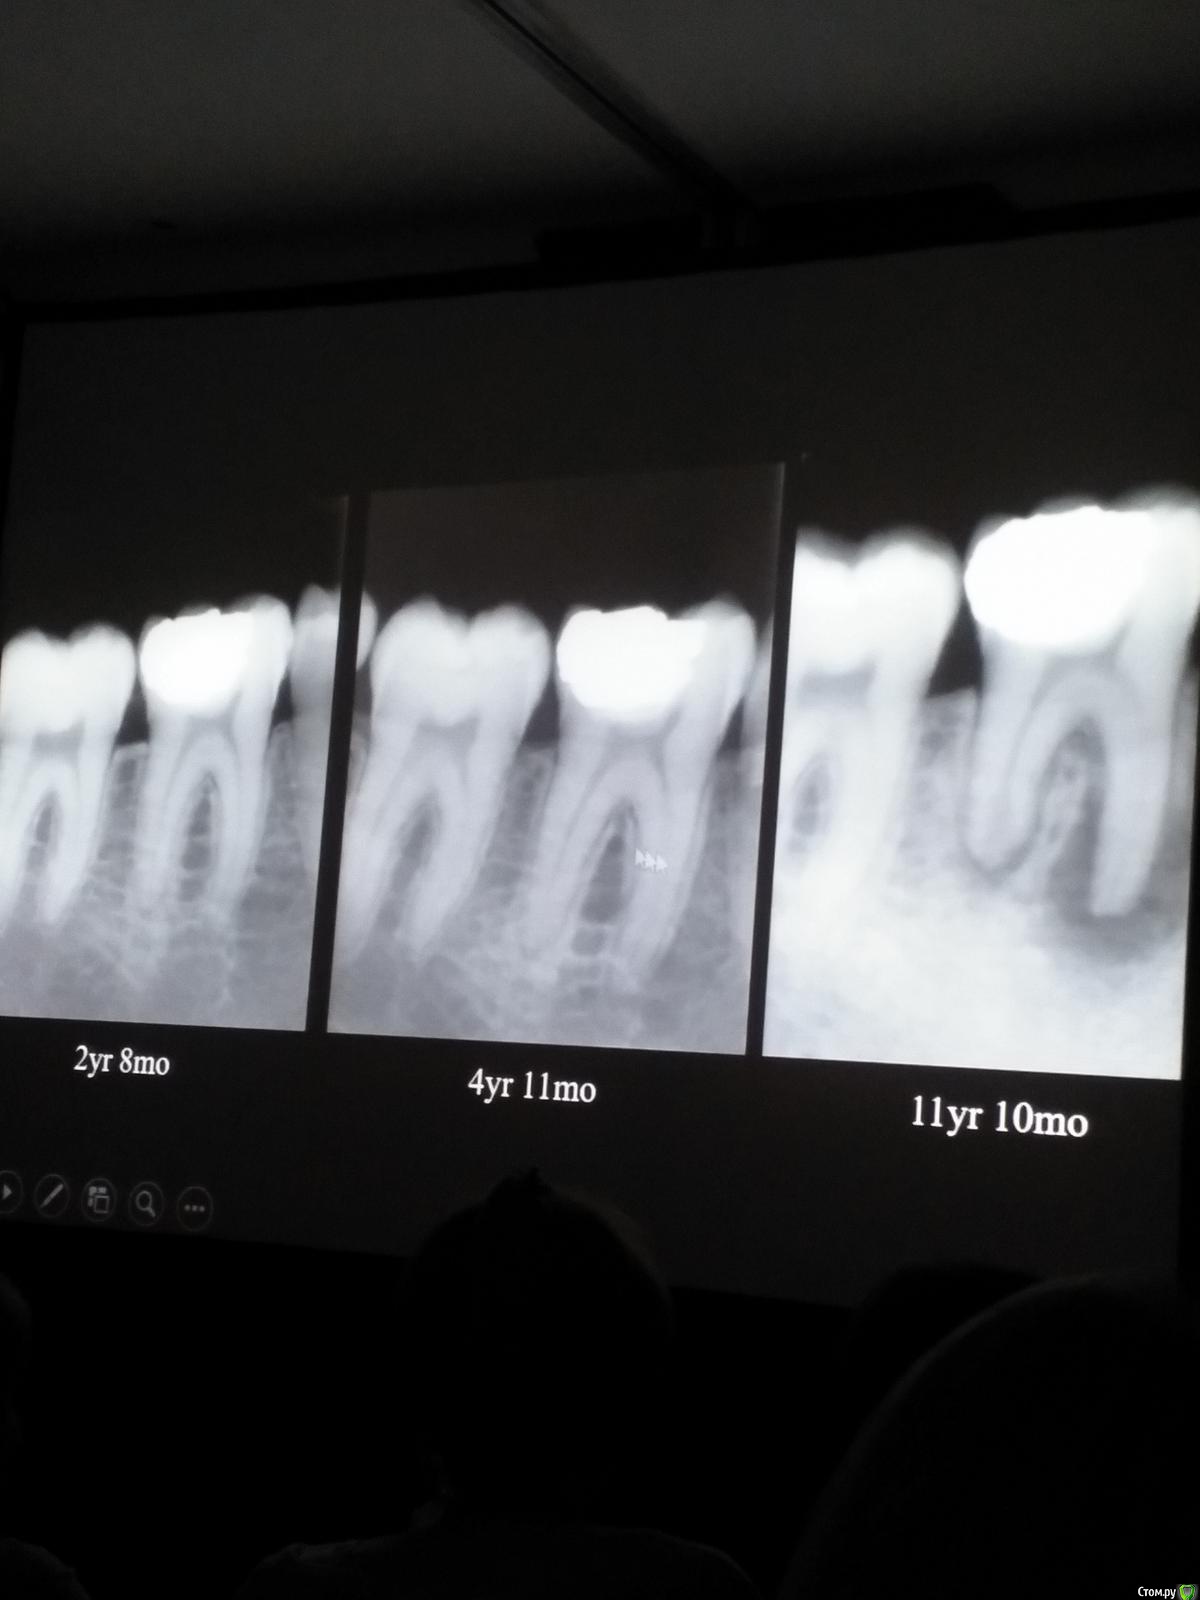

Популярный пост Kolchanov Опубликовано 11 марта, 2017 Популярный пост Поделиться Опубликовано 11 марта, 2017 (изменено) Товарищи, скажу я вам...........Вкратце. Может я где-то что-то и приврал, надеюсь, кто еще был, поправят. Честно говоря немного прибалдел от уровня Доктора. Очень, очень высоко! Приедет еще раз, пойду еще. 1) Фиссуры зондирует острым зондом и выпиливает все дотла. По факту у него уже пломбы, а не герметизация.2) Bite-wing у первичных пациентов всегда.3) Если кариес диагносцирован, то лечить его, пофиг какой он там. Эмали, дентина…4) Препарирует до твердого (или до вскрытия J ). CAD, СID… в топку. Кариес маркером не пользуется, проверяет острым зондом/экскаватором. Вычищает все дотла. Считает, что даже небольшое количество бактерий в дентине под пломбой вызывают хроническое воспаление в пульпе. С его слов у него на контроле где-то 500 вскрытий, не удивительно при таком подходе к очистке.5) Тщательная изоляция. Коффер порвался – меняет. Большое значение герметичности реставрации. под замену6) Критерии обратимости и необратимости.Гистологически, обратимый тот, что без абсцессов в пульпе, но клинически это понять нельзя, только предположить.Здесь был бы обратимый, если бы не удалил. Нет микробов в пульпе. Линия - граница обработки.Покрытие 27 лет назад. Dycal, СИЦ, композит. От дайкала одно воспоминание.7) Вскрылись. Размер перфорации, возраст и прочее не играют роли, важно только состояние пульпы, т.е. диагноз.Примеры перфораций.8) Кровотечение останавливает стерильным ватным шариком. Если останавливается, то покрытие, если нет, то пульпотомия или пульпэктомия.9) Использует гидроокись кальция (порошок), перекрывает Dycal или СИЦ. Потом восстановление Нередко под IRM, потом все убирает (через пару-тройку месяцев) и смотрит, что получилось. Порой приходится повторять! Использует и МТА, его тоже убирает.10) Наблюдение 6мес, 1 год, 2…. Все может провалиться и через месяц и через 24 года.Примеры проваловНиже - 24 года спустя появилась дуля. 11) Неравномерная облитерация полости зуба на RG (после покрытия) – признак текущего хронического воспаления, где-то остались микробы. Рекомендует эндо.12) Мостик который образуется – это не дентин! И одонтобласты не регенерируют и новые не образуются. Что это такое он и сам не знает, но раз это твердые ткани, то и наплевать.Вот фиолетовое это дентинные опилки вмурованные в розовую ткань бог знает кем сформированную.13) Пульпотомия в зубах с несформированной верхушкой и в сформированных, при подозрении на частичное поражение коронковой пульпы. Иссекается стерильным алмазным бором часть пульпы, гидроокись, временная пломба на 90 дней, после повторное раскрытие, оценка результата, восстановление в случае формирования твердых тканей. Гипохлоритом можно мыть, можно не мыть, если мыть, то 0,5-1%.14) В апикальной части пульпа чаще витальна, чем нет.15) Периапикальные поражения возникают по причине поступления токсинов микробов с током крови, а не самих бактерий.16) За апикальные расширения в полностью некротических случаях. Надо механически отодрать биопленку и срезать инфицированный дентин. На ирриганты надежды мало.17) Биопленка на поверхности в 6% случаев.Синенькие пид@расы18) Обработку проводить нежно, краун-даун. Чередовать с H-файлом, чтобы посмотреть докуда распространяется некроз.19) Патенси в витальных кейсах не колоть, сохранять витальную пульпу в констрикции!Формирование еще большего сужения в констрикции за счет сохранения витальной пульпы. Изменено 11 марта, 2017 пользователем Kolchanov 31 Ссылка на комментарий

Популярный пост Kolchanov Опубликовано 12 марта, 2017 Автор Популярный пост Поделиться Опубликовано 12 марта, 2017 Второй день.1) Дезинфекция зуба и раббер дама перед работой. Вначале установка системы, потом протирка тампоном 30% перекиси, потом протирка всего йодинолом. Потом преп, потом повторение и только потом доступ к к/к. Все старые реставрации надо убрать, кариес убрать, противник лечения через коронку.2) Гидроокись на неделю. Замешивает на стерильном физрастворе. При необходимости повторяет. Т.е. в случае сохранения свища, симптоматики, экссудации, запаха. Если свищ не исчезает после трех смен временных вложений, то хирургия.3) Пломбирует латеральной компакцией. Лучше контроль длины обтурации.4) Высушивание канала стерильными штифтами, на рабочую длину минус 1мм. После высушивания штифт оставляется на 60с. в канале и должен выйти сухим.5) Определение рабочей длины. Витальные случаи. АЛ должен три раза дать одну и ту же картинку в определенной точке + проверка RG. Девитальные случаи. На АЛ полагаться сложно, т.к. из-за наличия резорбции констрикции может врать, больше ориентируется на RG.6) Использует ЦОЭ силеры. Резорбируются при незначительном выведении. Резорбируются в канале, позволяя закрыть апекс цементоподобной тканью. Вот так вот.Случаи исчезновения силера, как за пределами канала так и в канале7) Выведение материала (не важно какого) в большом объеме способно вызвать защитную реакцию тканей. Которая должна пройти спустя некоторое время. (иногда это будет 25 лет J Случай 1ый. Студенты наломали инструментов. Периодонтит на RG через год. Резекция и гистология. Бактерий не обнаружил. Да, маленькое замечание. Каждый препарат дает 500-600 срезов. И ищет он на всех. Объем работы, конечно….Случай 2й. Его собственный. Периапикальное поражение, обнаруженное на реколле через 10 лет зажило еще через 15.8) «Функционирующий зуб» считает результатом неприемлемым. Осталась инфекция с которой надо что-то делать. То, что бактерий можно замуровать в дентинных трубочках и под пломбировочным материалом, считает неправильным. Продукты метаболизма один фиг будут просачиваться и могут поддерживать реакцию воспалительную.Случай. Синее – маленькая кучка микробов, предположительно, препятствовавших заживлению очага.9) Биопленка на поверхности корня может принимать вид кальцификатов (камней) и тут уже только хирургия в помощь. При длительном существовании свищевого хода, например.Черное - это камни вокруг апикального отверстия. И гистология их с кучей синих микробов.Здесь камни на фуркации и отсутствие заживления и свищ даже после ретроградной обработки и пломбировки.А здесь вообще чертова уйма камней. И зацените разветвление канала в этом боковом резце (последнее фото препарата). 10) Реваскуляризация.В некротических случаях дентина не образуется, т.к. одонтобластов нет и не будет новых. Образуется та самая бог знает какая ткань, которая даже и с корнем не связана может быть. Суть здоровый дентикль-петрификат. А в витальных это не реваскуляризация, а обычное формирование корня. Так что нечего тут.11) Трещины дентина.Советует расшивать, братья и сестры. Без фанатизма, если нет симптоматики, но, по возможности максимально. Если есть симптоматика, то там уже по обстоятельствам. Чертова уйма микробов там и ползет, ползет к пульпе. Надеюсь, что еще раз этот замечательный Доктор приедет. Схожу с удовольствием. 2 23 Ссылка на комментарий

zubolekar163 Опубликовано 10 апреля, 2017 Поделиться Опубликовано 10 апреля, 2017 (изменено) Больше всего в вебинаре Рикуччи меня убило то что он ЦОЭ силером пользуется.А кое кто нам тут про биокерамические силеры рассказывает Изменено 10 апреля, 2017 пользователем zubolekar163 Ссылка на комментарий